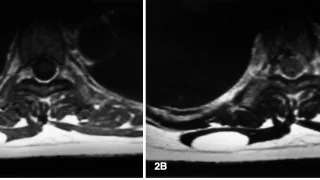

午前の病院での仕事今朝も小雨.気温は, 6 ℃.8時前に病棟に上がって, 昨日後輩医師の執刀で関節鏡下外側半月板縫合術が行われた高校生の患者さんの経過を確認.問題なく, 今日からリハビリを開始できそうです.8時から朝の病棟回診.9時前に外来...